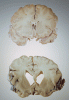

Differences in a healthy brain (top) and a diseased one (bottom) clearly show the damage wrought by Alzheimer’s.